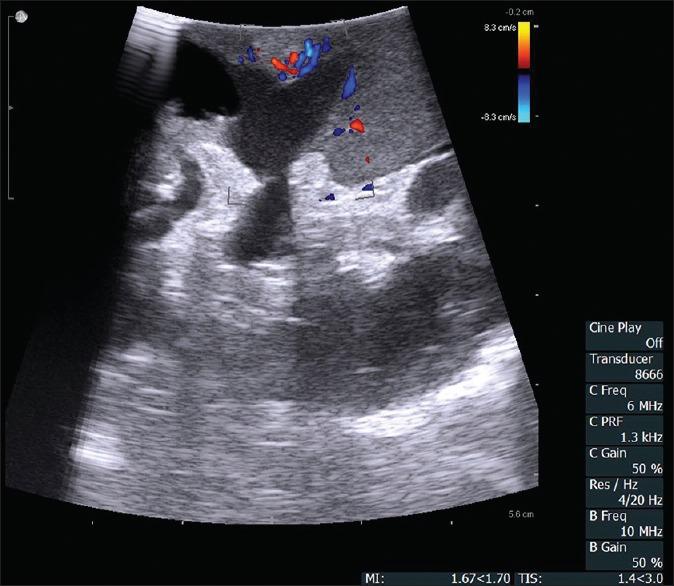

From January 2013 to December 2018, RLPN with ILUS was performed on the recent 199 patients in our center (two patients received bilateral RLPN due to suspected malignancy of both right and left sides), and the relevant clinical and follow-up data were retrospectively reviewed. Among them, 119 patients were male and 80 were female; the age of patients was 53.4 ± 12.3 years. Of all the renal tumors, 105 were located on the left side and 96 on the right side with a RENAL score of 6.6 ± 1.7. All the patients were diagnosed as or suspected of having a renal tumor by preoperative imaging examination. The ILUS was applied in all the operations to help locate the tumor, delineate the boundary, clarify the diagnosis, observe the blood supply, and so on.

RLPN with ILUS in these 199 patients was successfully performed without conversion to open surgery. All surgeries were completed in 90.2 ± 21.7 min, with 73.6 ± 89.2 mL for estimated blood loss, and 19.3 ± 5.6 min for warm ischemia time. The tumor size was 3.6 ± 1.5 cm, and all the surgical margins were negative. The drainage days and postoperative hospital days were 4.7 ± 2.3 and 6.1 ± 2.3, respectively. The preoperative creatinine was 69.7 ± 19.4 μmol/L compared with 61.6 ± 12.7 μmol/L measured 1 month postoperatively. There were 17 cases of renal cell carcinoma no more than 1 cm, and they were resected without artery clamp or a large amount of blood loss. Satellite tumors were confirmed in 12 cases, of which 8 were not detected by preoperative examinations and finally found by ILUS during surgeries.

ILUS can alleviate the difficulty of preoperative diagnosis, facilitate surgical dissection, and improve the effect of nephron-sparing surgeries. Due to its great advantage, ILUS should further be promoted and applied.